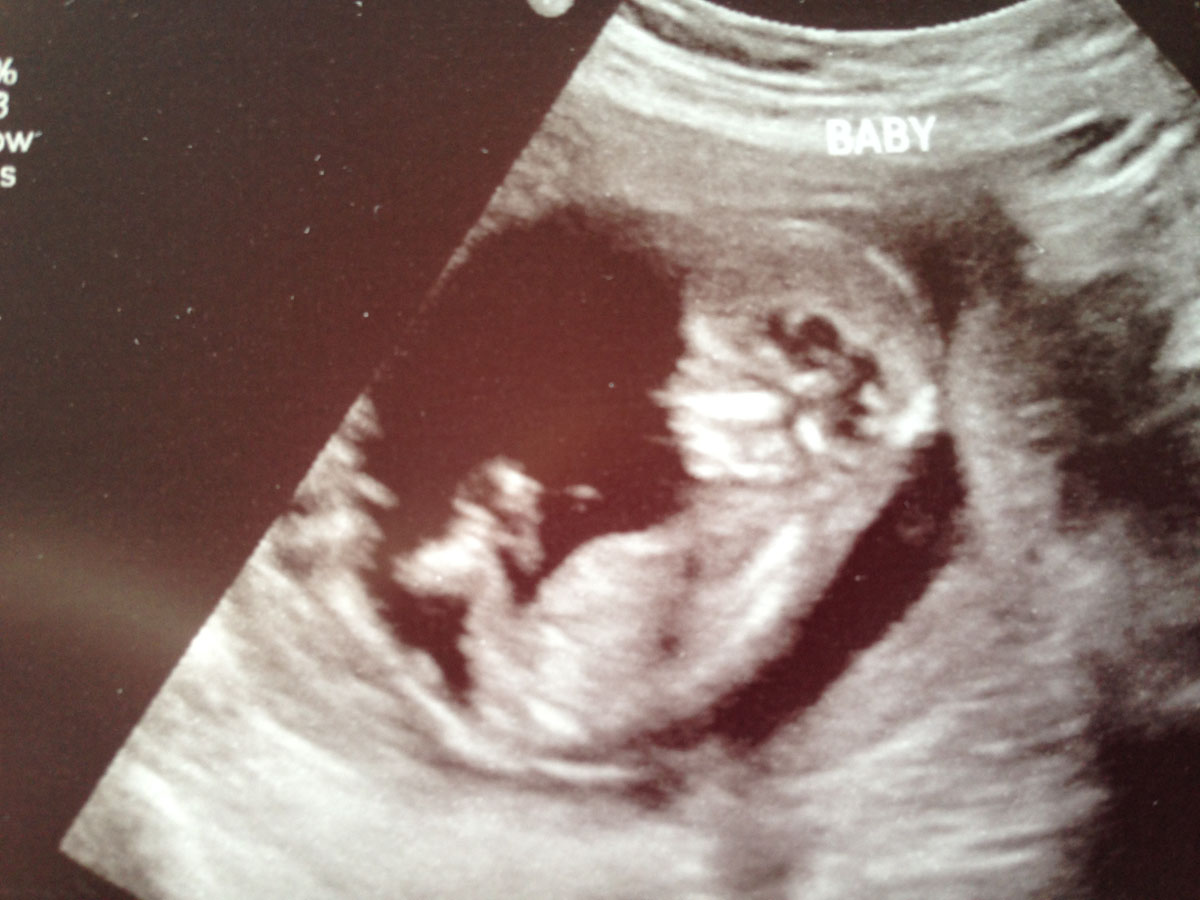

I've been reading up on nubs for weeks and still really have no idea what I'm looking at. I'd reeeally appreciate any guesses on these!

I'm not seeing any clues sorry :)

No nub

no nub sorry legs are in the way!

Skull looks girlish though !